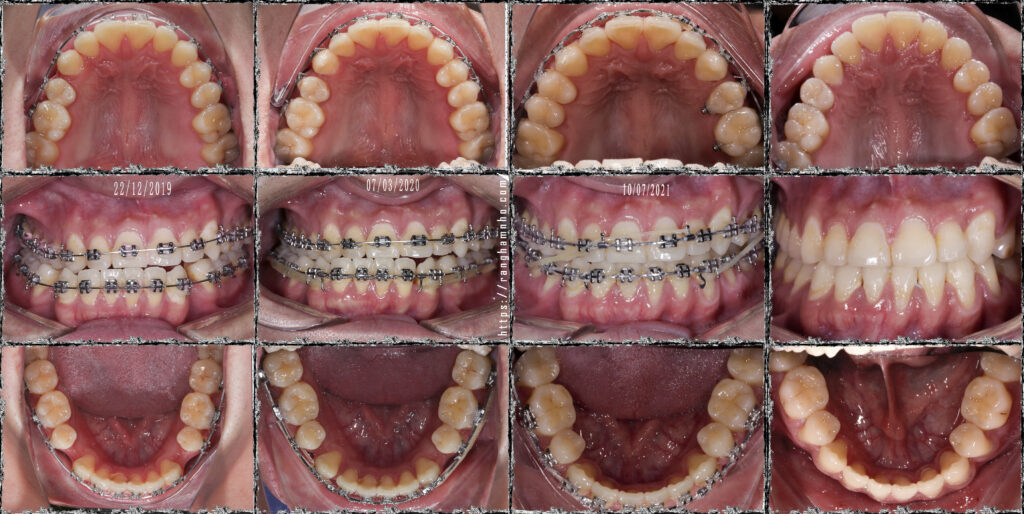

BN nam sinh năm 1994 khớp cắn hạng III, răng chen chúc. BN có sự phát triển không đồng đều của xương hàm dưới hai bên dẫn đến biến chứng lệch mặt. Kết hợp cả yếu tố sai khớp cắn do răng làm hàm dưới vừa lệch do xương lại vừa lệch do thích nghi chức năng. BN đã được nhổ 3R4 để giải quyết vấn đề chen chúc răng và kéo lùi nhóm răng cửa dưới.

Tình hình khi gặp gỡ: còn nhiều khoảng nhổ răng, khớp cắn ngược răng cửa, cắn chéo nhóm răng hàm cung 1. Đường giữa hàm dưới lệch nguyên 1 răng cửa. Mặt thẳng lệch rất rõ, cằm đưa hẳn sang bên phải.

Xử lí: Đóng khoảng hàm dưới đến mức vừa phải để giải quyết cắn ngược răng cửa. Bẻ MEAW trên TMA 17×25 định vị lại vị trí xương hàm dưới. Sau đó chuyển lại kĩ thuật dây thẳng để kết thúc sau gần 2 năm.

Kết quả: đường giữa gần như thẳng, xương hàm dưới định vị về vị trí bình thường. Khuôn mặt cải thiện khá so với trước điều trị nhưng không thể hoàn hảo do căn nguyên sai lệch kết hợp đến từ sai lệch xương ![]()